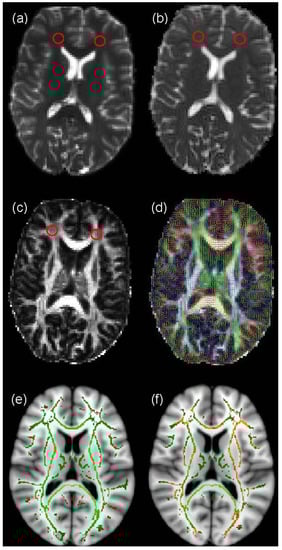

DT-MRI measures the random motion of water molecules in vivo. In free water, diffusion is isotropic, that is the movement of water molecules is equal in all directions. Conversely, in the brain’s WM the motion of water molecules is restricted by axonal membranes and myelin, so diffusion is not equal in all directions, and is therefore anisotropic []. This random motion can be represented mathematically by the diffusion tensor D []. This 3-by-3 symmetric matrix, which is measured in each imaging voxel within the brain, can be decomposed into three eigenvalues and three eigenvectors which indicate the magnitude and directionality of diffusion in three orthogonal directions []. In WM, since water molecules diffuse preferentially along the principal fibre direction, the eigenvector corresponding to the largest eigenvalue is taken to represent the fibre direction. This information can be used in a technique called tractography (see below) to examine connectivity between different brain areas []. Furthermore, the three eigenvalues can be employed to generate biomarkers of WM structure, the commonest of which are the mean diffusivity (MD), which measures the magnitude of water molecule diffusion, and fractional anisotropy (FA), which measures its directionality coherence (Figure 1a–d); FA takes values from 0, which indicates completely isotropic diffusion, to 1, which indicates completely anisotropic diffusion [].

ROI analysis usually involves an expert observer hand-drawing features, such as focal lesions, on structural MRI data and transferring them to co-registered DT-MRI data to measure diffusion biomarkers (Figure 1a–c). Although this is most often performed manually, automated methods of ROI placement have been suggested to improve objectivity; see Snook et al., (2007) [] for more details. ROIs are used to restrict the areas of the brain in which measurements are made, thereby reducing the need for statistical corrections for multiple-comparisons across the whole brain. ROI analysis is also useful for measuring the relative size of anatomical features between subjects or groups. Once the ROIs are selected MD and FA can be compared in these regions between subjects or time-points. A considerable advantage of the ROI technique is that it allows the investigation of differences in native space within individual brains, so details are not lost in the registration process to a standard space template, as occurs in voxel-based methods (see below). However, ROI analysis does require a strong hypothesis in order to select suitable regions for comparison, along with control regions. ROI analysis is also extremely labour intensive as manual placing, visual inspection and editing is required for each of the selected regions to ensure the same structure is measured in each person.

Figure 1.

An example of Diffusion Tensor Magnetic Resonance Imaging (DT-MRI) analysis. The figure displays maps of (a) T2-weighted signal intensity, (b) mean diffusivity (MD), (c) fractional anisotropy (FA) and (d) colour-coded principal diffusion direction overlaid on FA from a normal volunteer obtained using FMRIB’s Diffusion Toolbox (FDT) analysis pipeline []. Region of Interest (ROIs) placed in frontal white matter (WM) in (a) and transferred to (b) and (c) for measurement of MD and FA are indicated by red circles. In (d), the colours indicate water molecule diffusion occurring in the right/left (red), anterior/posterior (green) and superior/inferior (blue) directions. Also shown is an example of voxel-based analysis of FA data obtained using FSL’s Tract-Based Spatial Statistics (TBSS), specifically (e) a WM skeleton overlaid on an Montréal Neurological Institute (MNI) standard brain, and (f) voxels on this skeleton which are significantly different between two populations under study, represented in orange.

Voxel-based analysis can be used to investigate WM differences on a voxel-by-voxel basis across the brain. TBSS [], which was specifically designed to analyse DT-MRI data by reducing misregistration artefacts between subjects and partial volume averaging of GM and cerebrospinal fluid signal with WM [], is currently the closest to a standard analysis method for DT-MRI. In TBSS, the FA map for each participant is registered to a standard space template, a skeleton created indicating the centre of each WM tract, and then statistical analysis performed on a voxel-by-voxel basis to test for group differences (see Figure 1e,f). Due to the requirement that corrections are performed for multiple comparisons across the many hundreds of voxels that constitute the WM skeleton in each subject, TBSS is a relatively conservative analysis technique, typically requiring upwards of 20 to 30 subjects to provide robust significant differences between groups. Furthermore, the requirement that each subject’s FA data is registered to a standard space template may cause loss of small individual differences that are present in the native space data. Nevertheless, it is entirely automated and can be used to look at whole brain WM differences in a hypothesis-free manner.